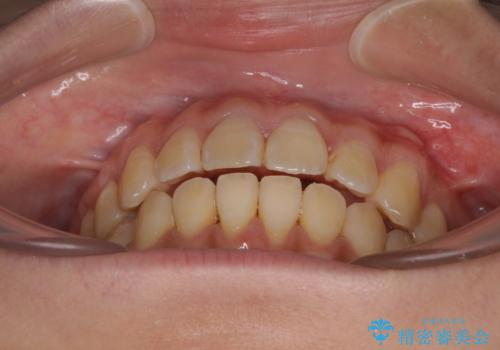

舌の突出癖による開咬と前歯の突出 インビザライン矯正治療

- 上下前歯の非接触と叢生を気にして来院された患者様です。

開咬の改善はインビザラインの最も得意とするところであるため、インビザラインを用いて矯正治療を行うこととしました。

治療開始直後に上顎前歯に激しい痛みが発現し、矯正治療を休んだり、マウスピースの装着時間を短くしたりと工夫をしましたが、残念ながら治療途中で失活していることが分かりました。

矯正治療の途中で前歯の根管治療とオールセラミッククラウンによる補綴治療を行い、その後インビザライン1セットを用いて細かい部分を仕上げました。